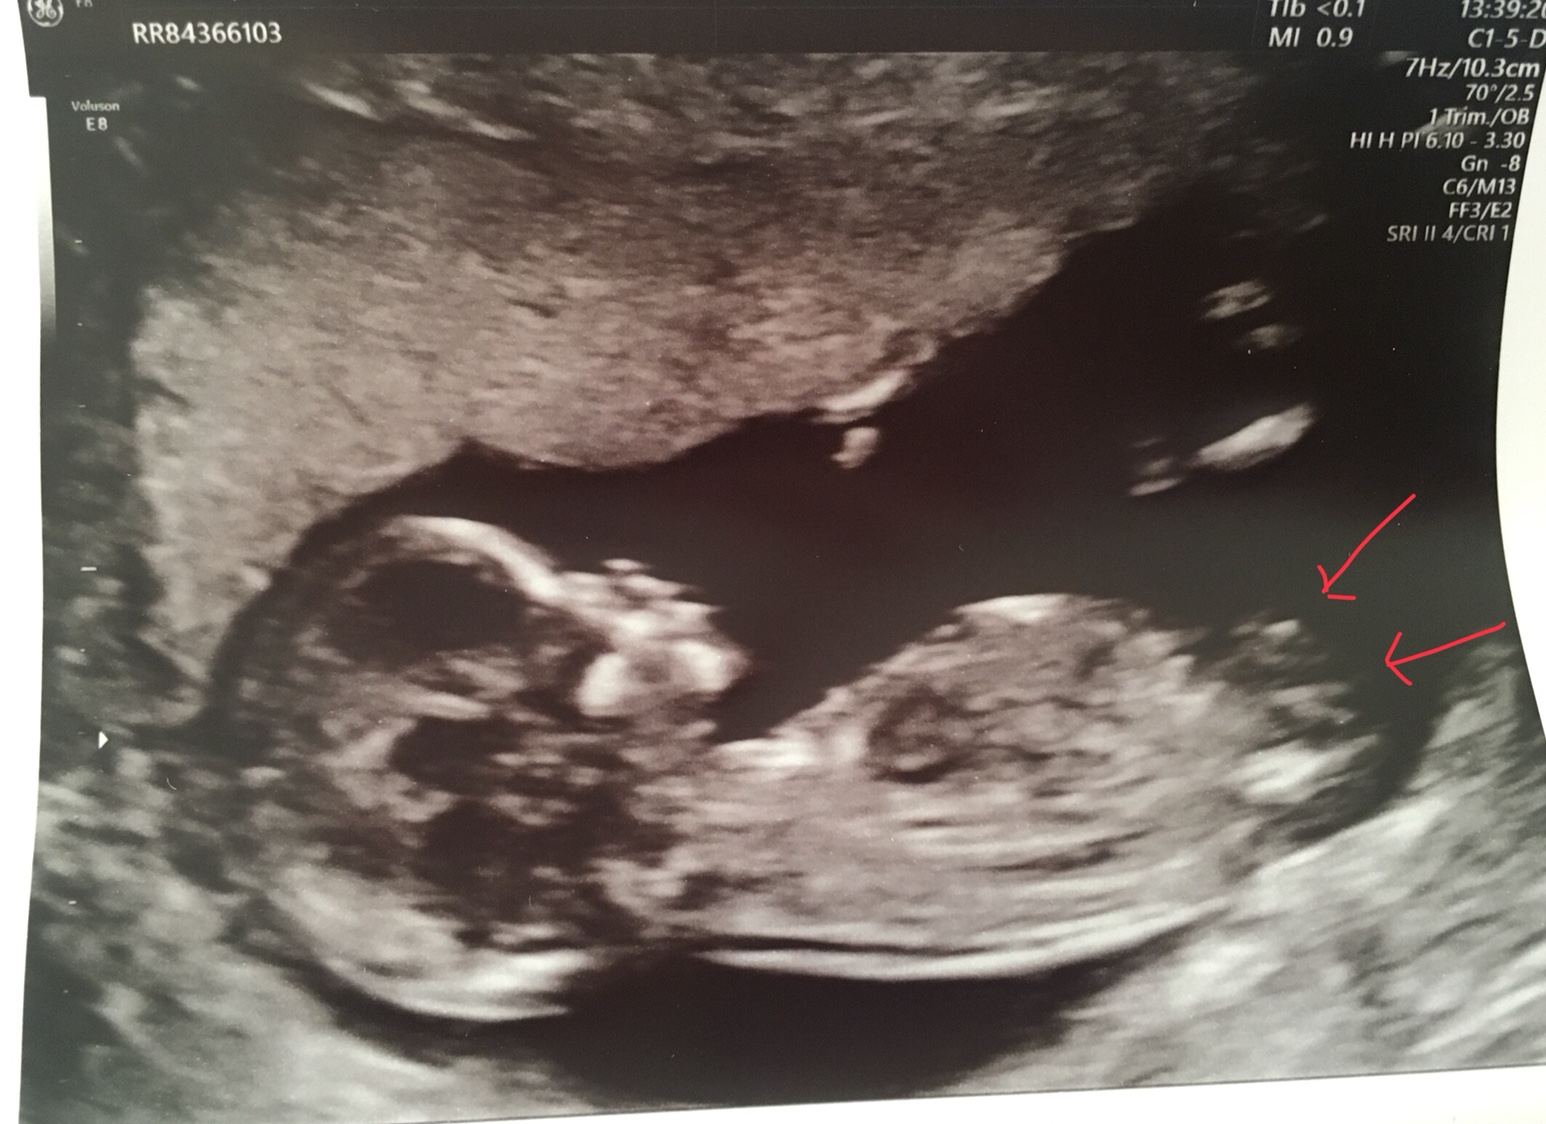

I am useless at nub / skull theory. Here is my 13 week scan. Any thoughts? I’ve looked at it and thought boy and then looked again and thought girl.

Attachment 40452